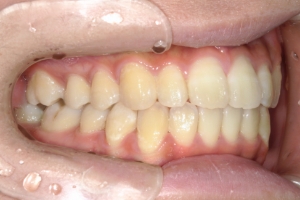

BEFORE

治療前

PROCESS

半年

AFTER

治療後

下の前歯が上あごの歯ぐきに当たるほど噛み合わせが深く、そのことが原因で上顎歯列の正中にすき間(正中離開)が生じていました。部分矯正ですき間を無理やり閉じても、噛み合わせが深いままでは治療後の再発リスクが高くなります。そのため全体矯正で奥歯の噛み合わせを整え、噛み合わせを浅くしつつ前歯を並べました。正中離開は戻りやすい傾向があるので、再発を防ぐため固定式リテーナーを推奨しています。